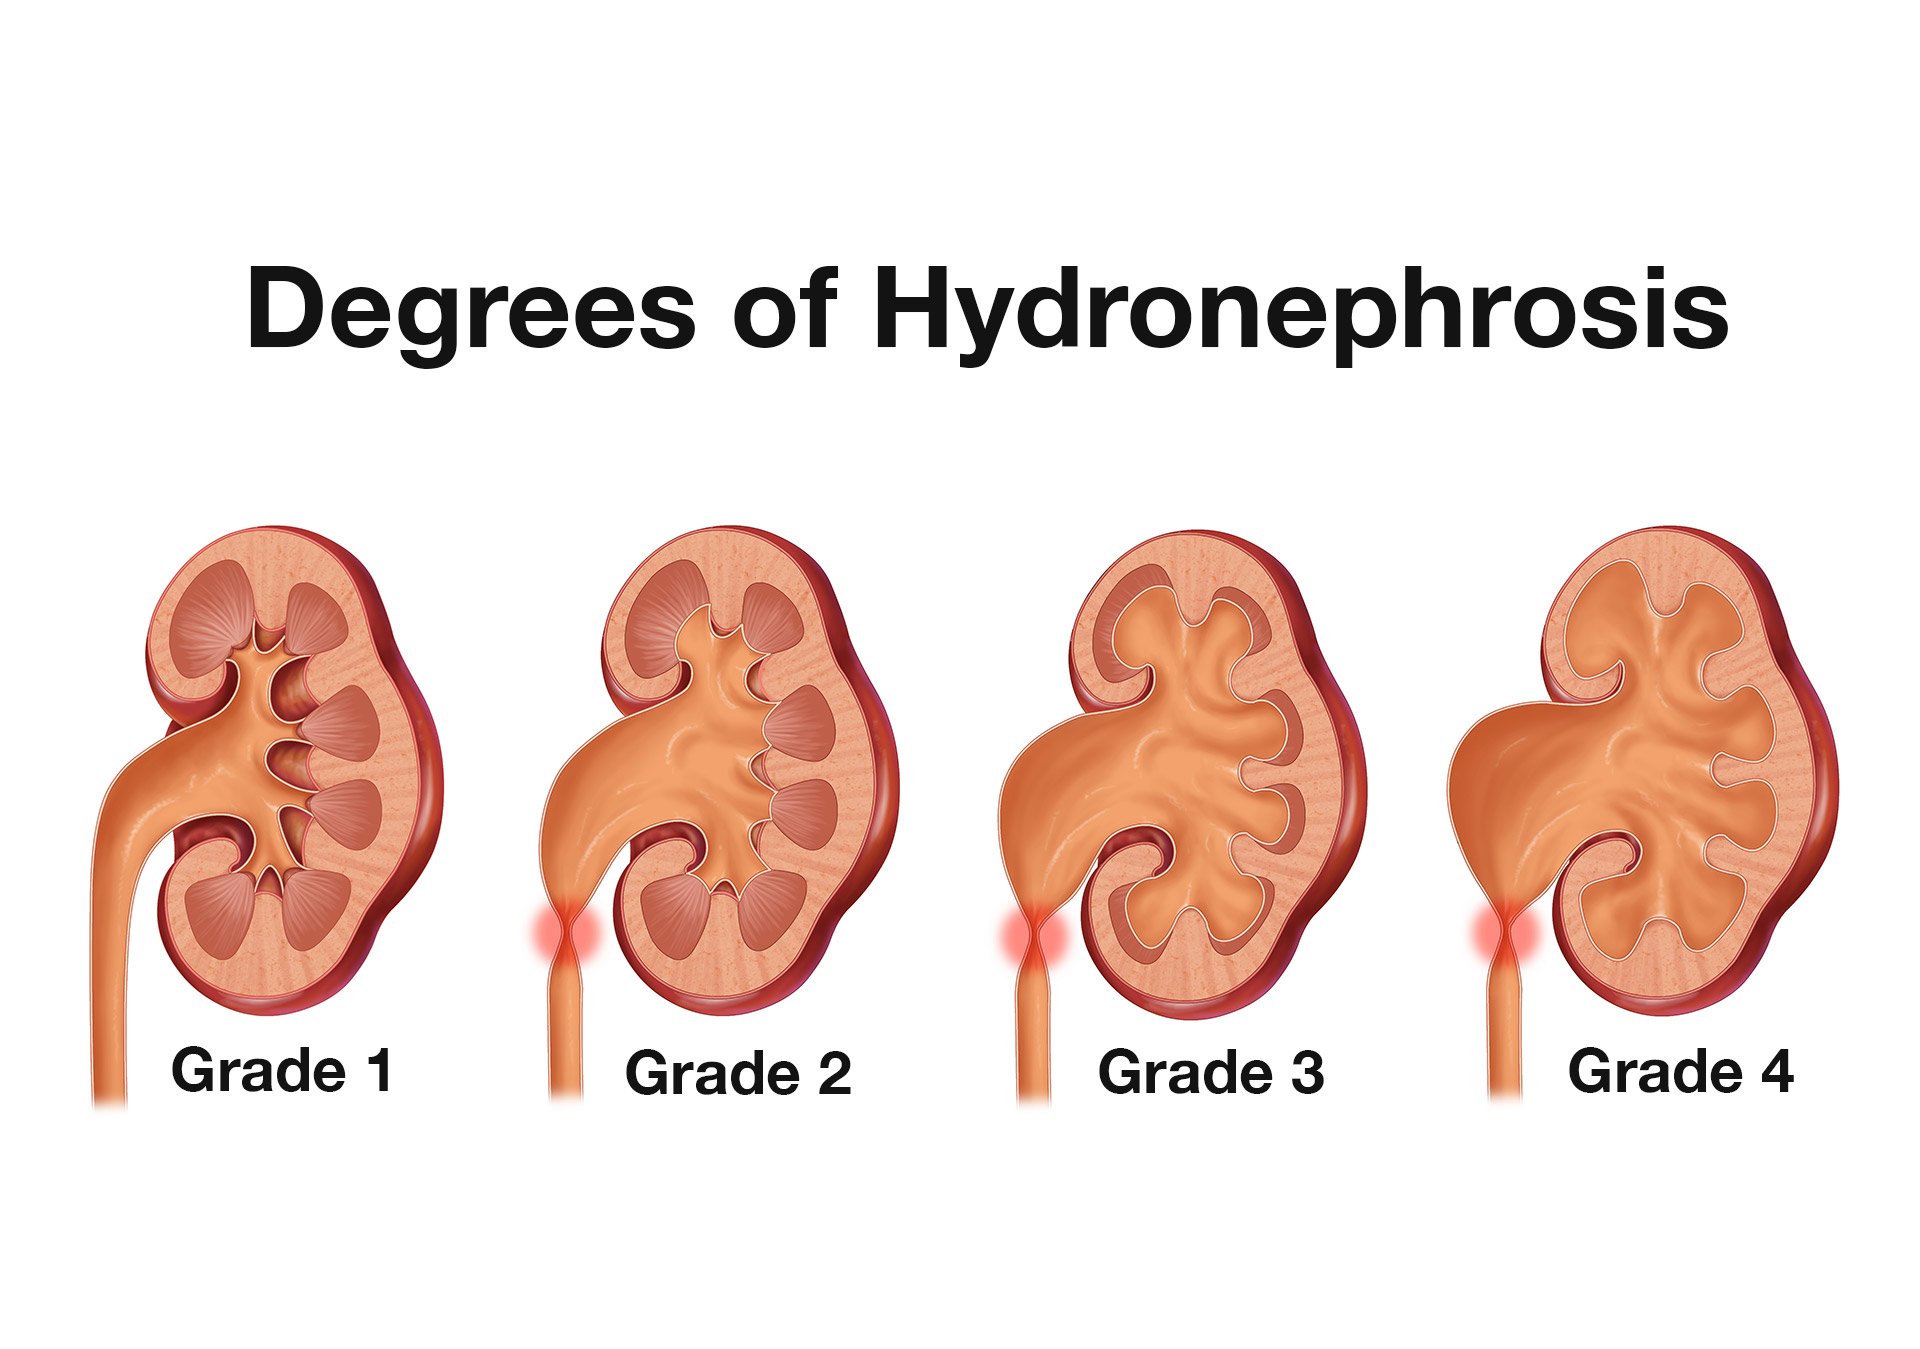

Интраренальная лоханка: рентгеновские снимки и примеры